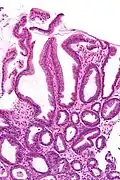

| Micrograph of a reactive gastropathy. H&E stain. | |

- Foveolar hyperplasia (black arrow), as a tortuosity in the "neck" region of the gastric glands.

- Scant or minimal inflammatory cells (white arrow), i.e. lack of large numbers of neutrophils and plasma cells..

- Smooth muscle hyperplasia in the lamina propria (in black oval).

The diagnosis is by examination of tissue, e.g. a stomach biopsy.